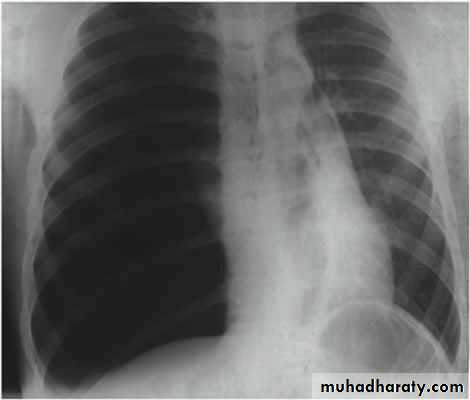

Fall from the 2nd floor